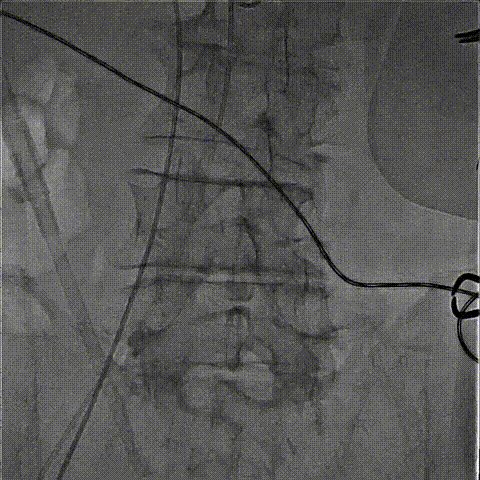

DSA下钢针穿刺心尖,建立心尖入路

输送系统沿加硬导丝进入

瓣膜初次释放,位置稍浅

目标深度:瓣环平mark点

部分回收后,调整瓣膜深度重新释放,瓣膜位置良好

无张力脱钩,瓣膜位置稳定

闭合输送系统后撤除体位,

收紧心尖荷包